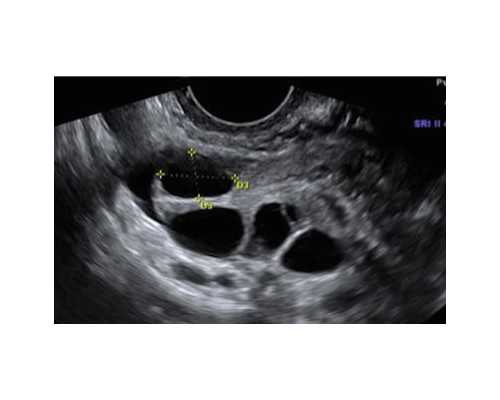

目前长沙所有医院都建立了卵子数据库,全国各省市还没有建立真正的卵子数据库。不过长沙部分试管医院已经开通了卵子试管供应渠道。虽然这些医院有资格进行卵子供应试管,但是由于国家卵子捐献者的严格条件,只有试管婴儿成功的患者自愿捐献给有需要的患者。但是一般来说,很少有患者自愿捐献,更多的患者只能自己使用卵子,所以试管婴儿需要的时间比较长。当然,为了缩短等待时间,有些患者会寻找其他可靠的卵子供应商,但一定要注意安全。